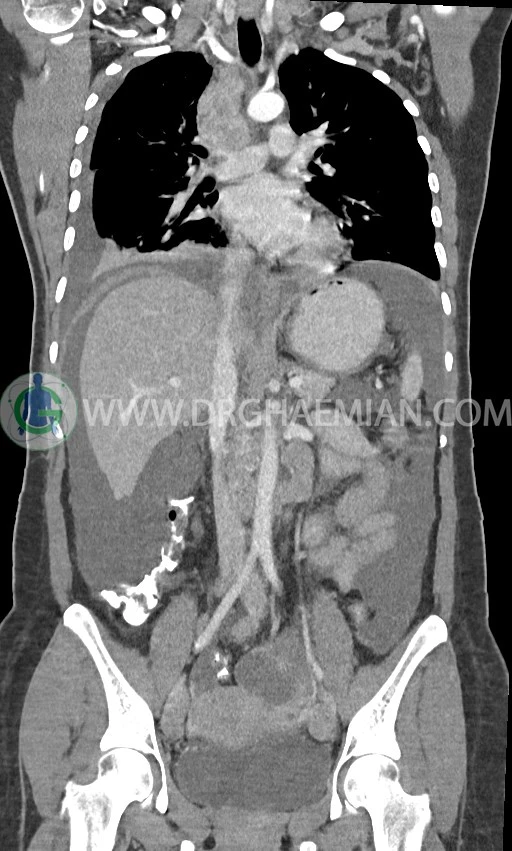

در سی تی اسکن اسپیرال ریه، مدیاستن و شکم و لگن با کنتراست خوراکی و وریدی (مولتی دیدکتور 16 با مقاطع ظریف و بازسازی های ساژیتال و کرونال) :

لنفادنوپاتی فراون با حداکثر SAD=25mm در مدیاستن

لنفادنوپاتی با حداکثر SAD = 12mm در سوپراکلاویکل چپ (level 4) و در level 6 و level 7

pleural effusion قابل توجه دوطرفه همراه با passive collapse سگمان های بازال (با شدت بیشتر در سمت راست)

لنفادنوپاتی فراوان در اطراف آئورت و IVC با حداکثر SAD= 25mm در دیواره دو طرف حفره لگن با حداکثر SAD= 20mm

مشهود است.